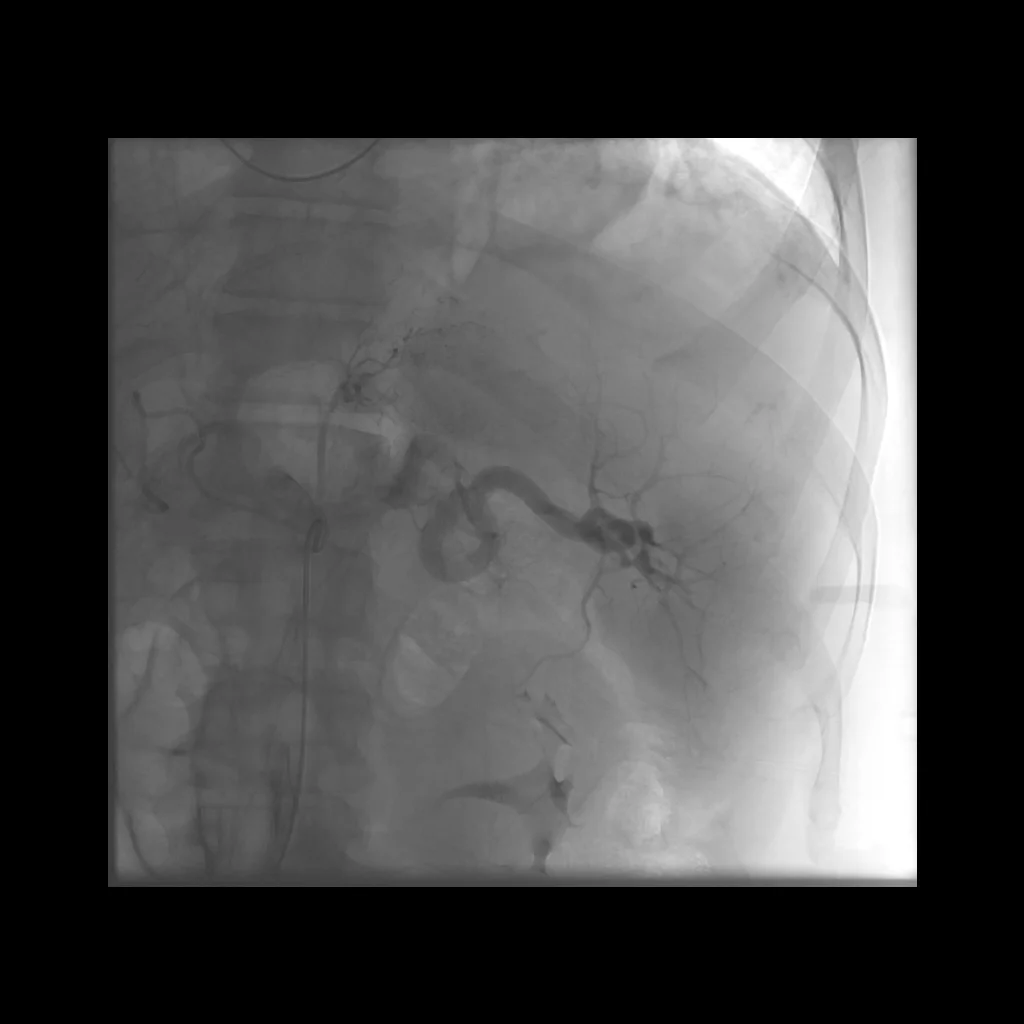

Trauma embolization: Case 3

31 year old male s/p MVA with LUQ pain and a splenic laceration.

Comment: There are several potential approaches to the endovascular treatment of splenic trauma. In this particular case, we saw a significant perisplenic hematoma on CT and angiography demonstrated active extravasation. While the tortuosity of the main splenic artery made it difficult, it was our goal to navigate the artery and attempt a selective catheterization of the bleeding artery, with the ultimate goal of selective distal embolization. In our opinion, distal embolization is the preferred approach when extravasation is seen. We reserve proximal splenic embolization for when distal embolization is not possible and when active extravasation is not evident on angiography.